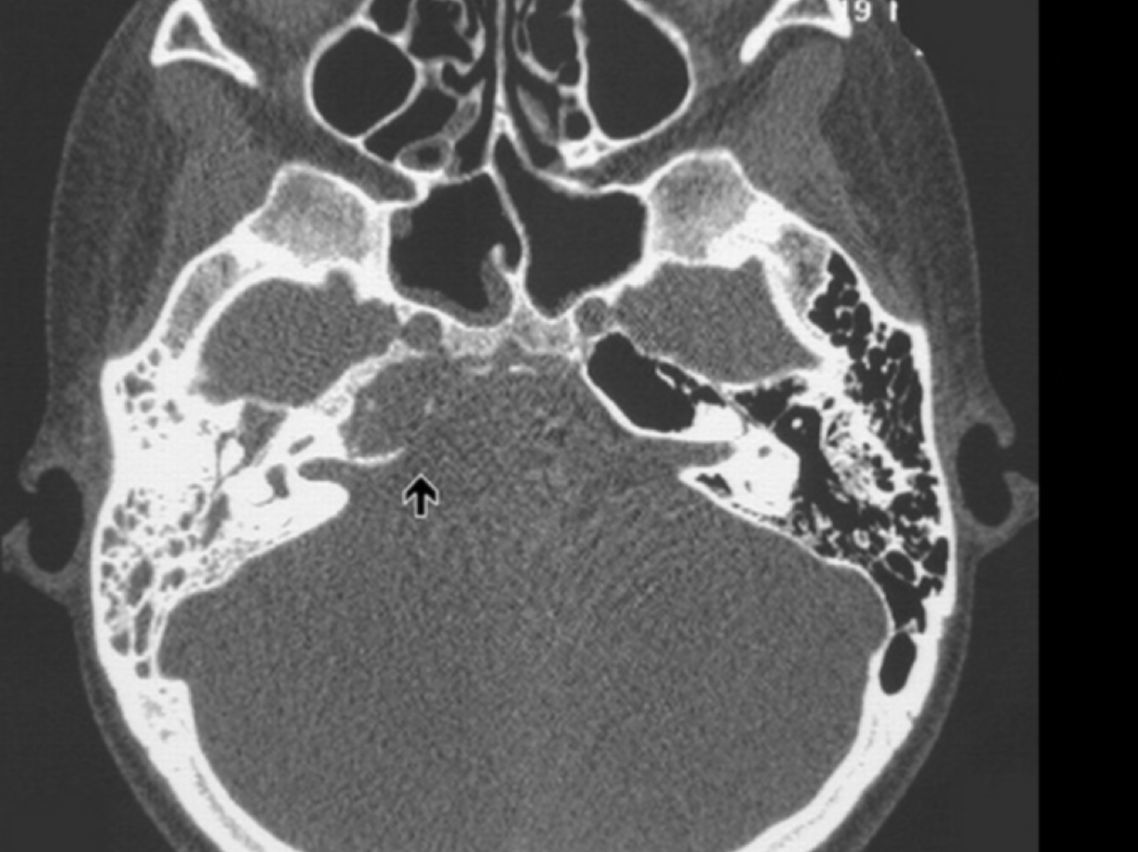

¿Cuáles son las pistas diagnósticas en la TC de la otitis media?

¿Cuáles son los hallazgos radiológicos en la TC de mastoiditis?

¿Qué abscesos se pueden formar secundarios a la mastoiditis?

¿Cuál es una pista característica del colesteatoma?

Destruye hueso